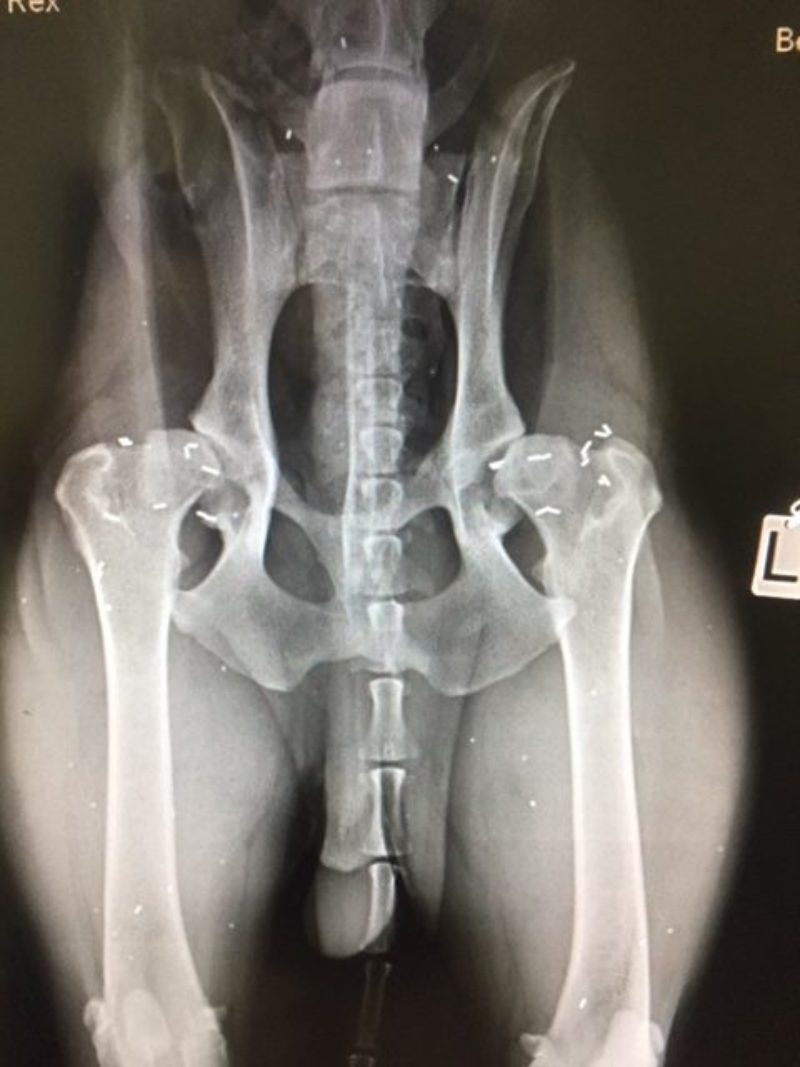

Fallbeispiel 1:  Rex, DSH-Rottweiler-Mix, 15 Monate alt

Rex hatte massive Probleme beim Aufstehen - und seine Hinterhandmuskulatur war wenig ausgeprägt. Er wurde mit neun Monaten in einer großen Klinik geröntgt. Dabei konnte eine schwere Hüftgelenksdysplasie (HD) festgestellt werden. Als Therapie wurde Abwarten vorgeschlagen. Später sollten dann zwei künstliche Hüftgelenke eingesetzt werden. Dem Hund ging es immer schlechter und wurde mir mit 15 Monaten vorgestellt. Die Triggerpunkte waren hochgradig schmerzhaft und in nur wenigen Monaten hatte sich beidseits eine starke Arthrose an den Hüftgelenken entwickelt. Die Goldakupunktur erfolge eine Woche nach der Erstvorstellung. Die Besitzer berichteten, dass Rex bereits zwei Tage nach dem Eingriff deutlich besser lief. Ihnen fiel auf, dass er jetzt in der Lage war, alleine auf die Couch zu springen, was er vorher nicht schaffte. Durch die Schmerzfreiheit konnte er sich viel aktiver bewegen, und die Muskulatur entwickelte sich im Laufe der nächsten Wochen hervorragend. Die Familie fuhr mit ihm an die Nordsee, wo er ohne Probleme mit anderen Hunden am Strand spielen konnte.